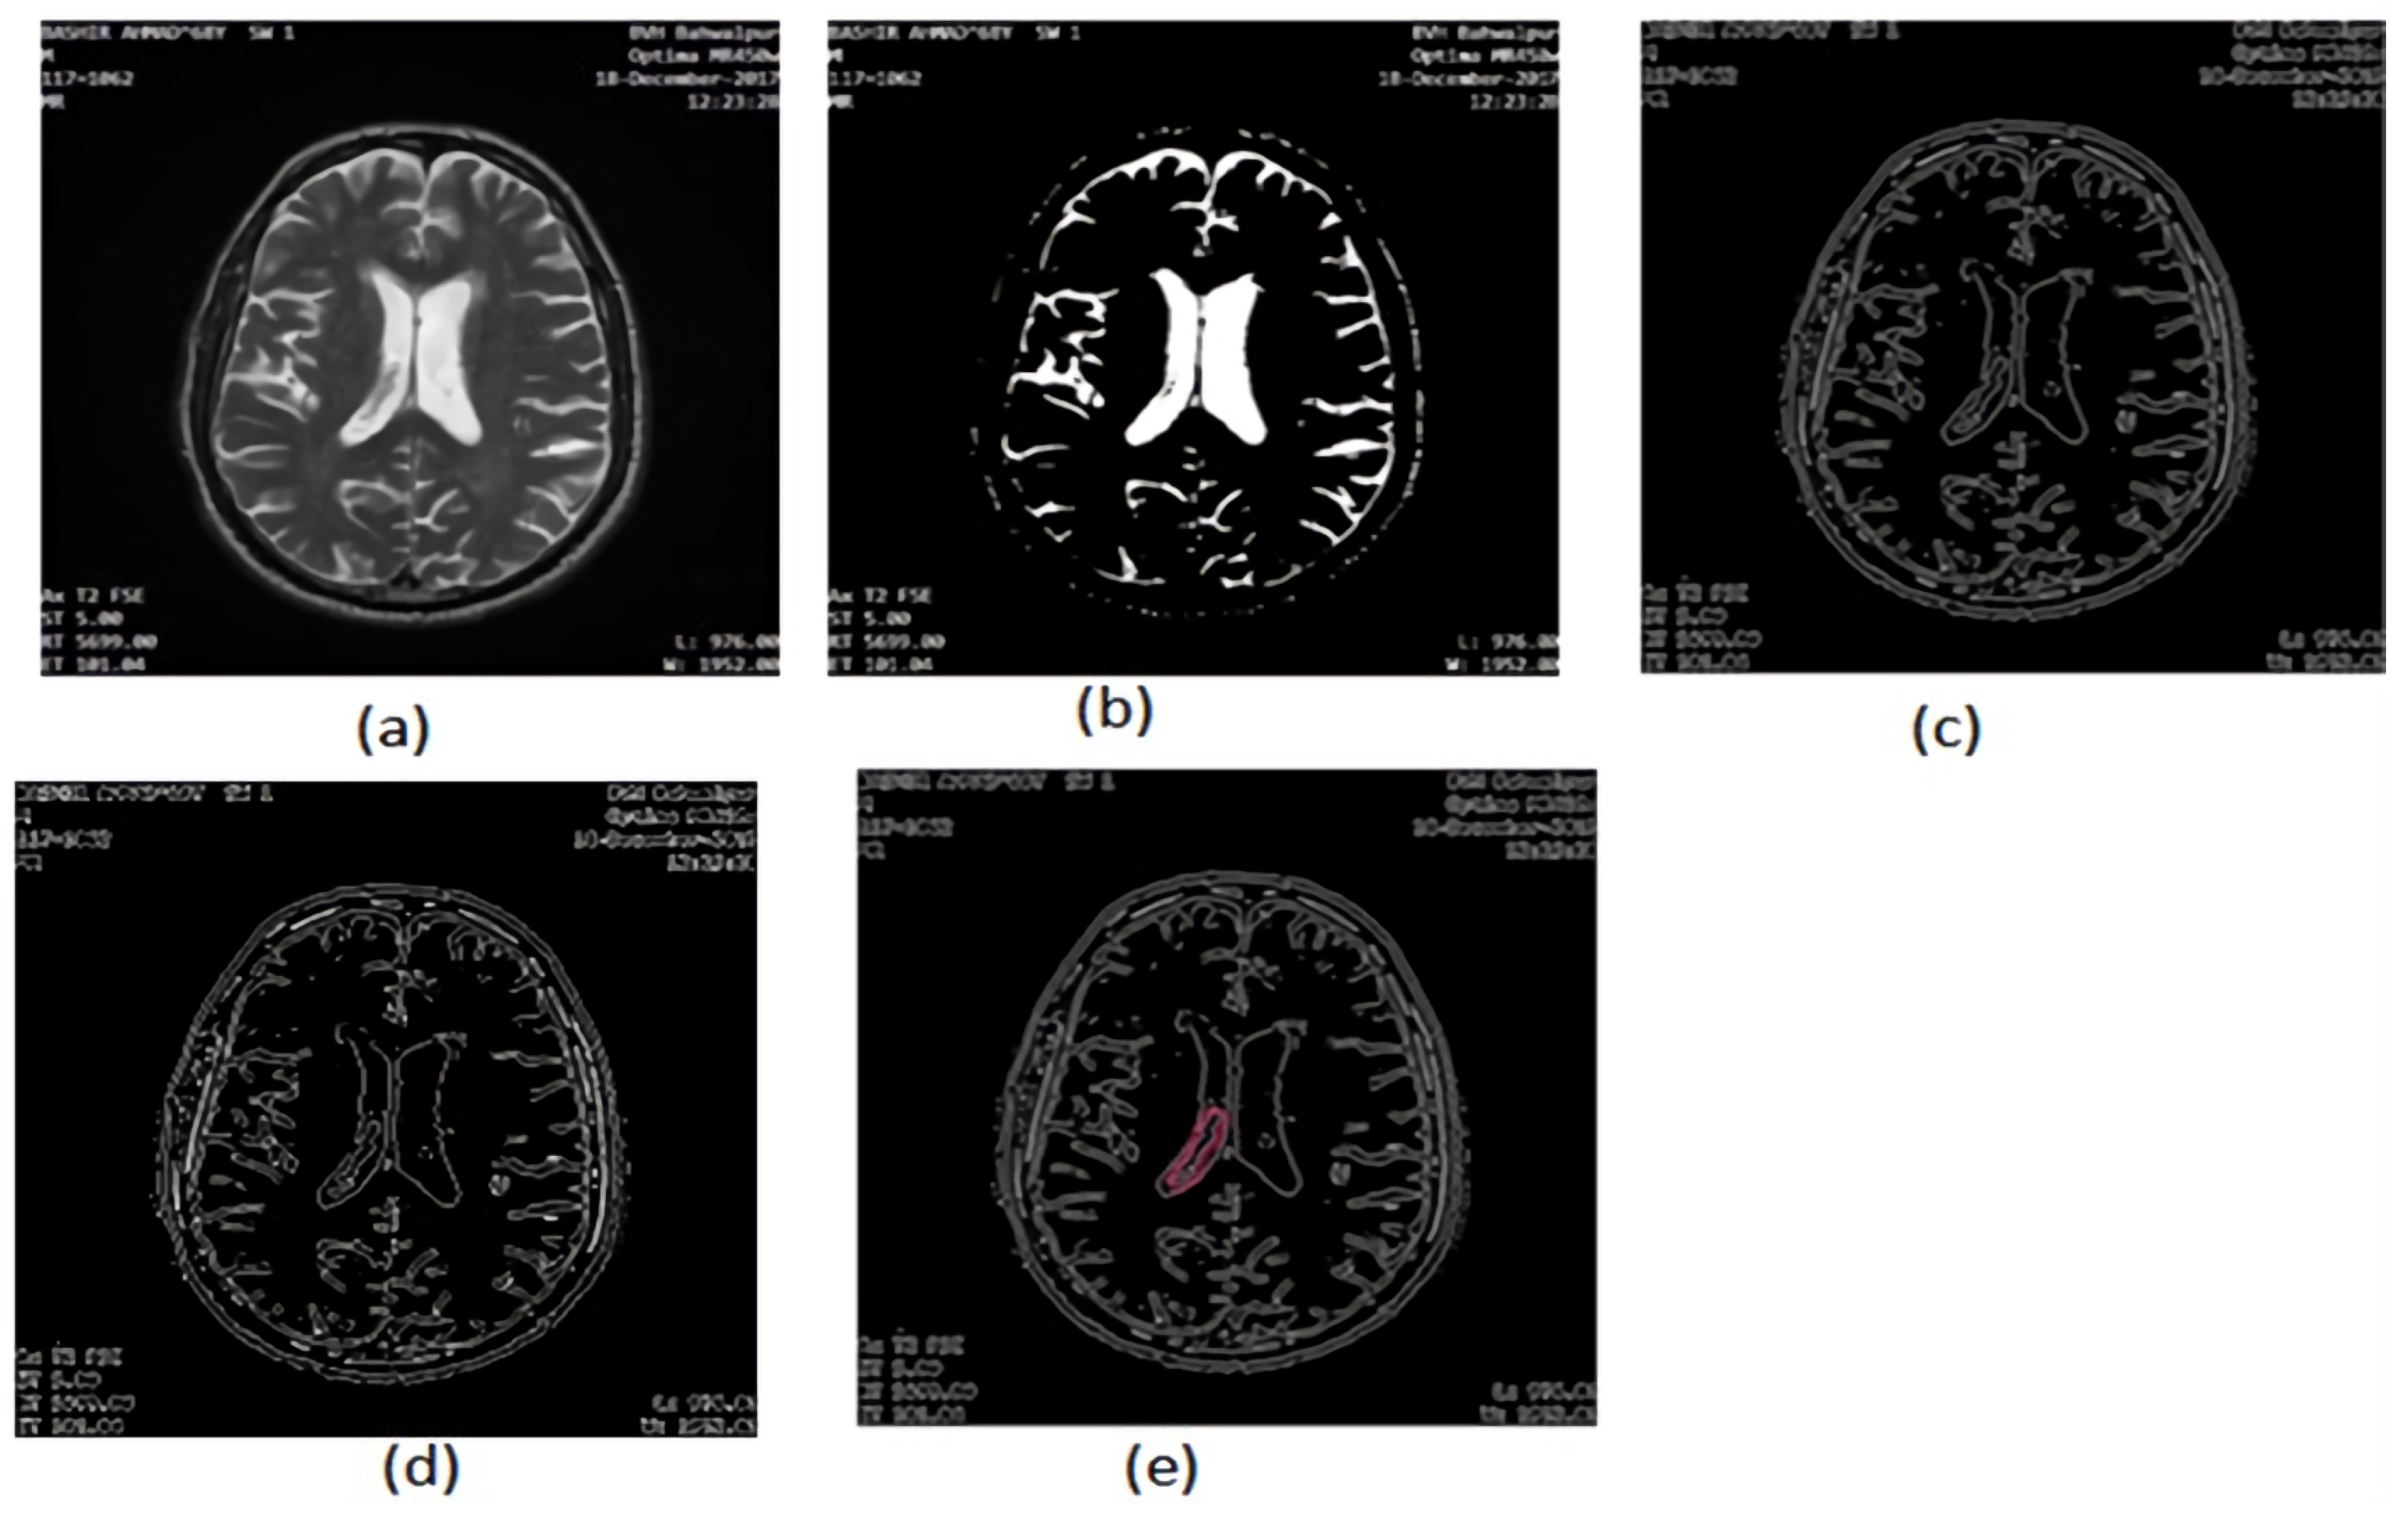

2.2.7. Area Segmentation using Watershed Algorithm

2.2.8. Region Masking and the Separation

2.3. Proposed a Colorized Method for Masked Area Colorization

- Strel: this command is used to create elements of morphological structure;

- Imerode: this function shrunk (eroded) the image;

- Imdilate: this function dilated the image and filled the areas after expanding.